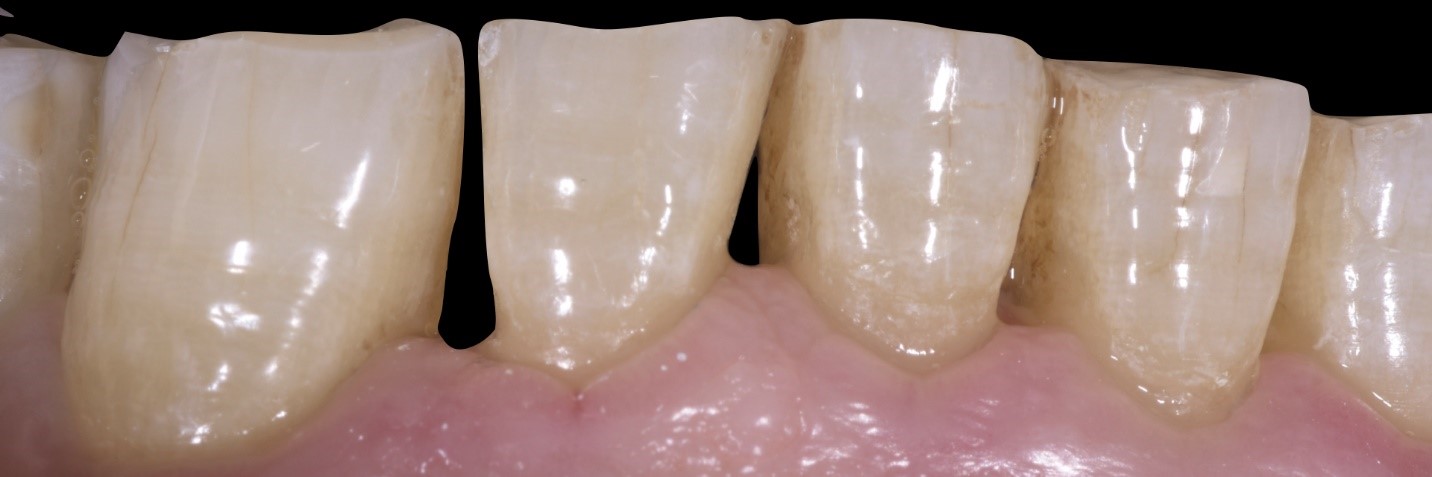

Fig. 3

Si noti la quantità di smalto residua che, anche negli elementi dentali maggiormente coinvolti, permette l’impiego di tecniche adesive con minima preparazione dentale ( tecnica MIPP, Minimally Invasive Prosthetic Procedure, by Fradeani Education).